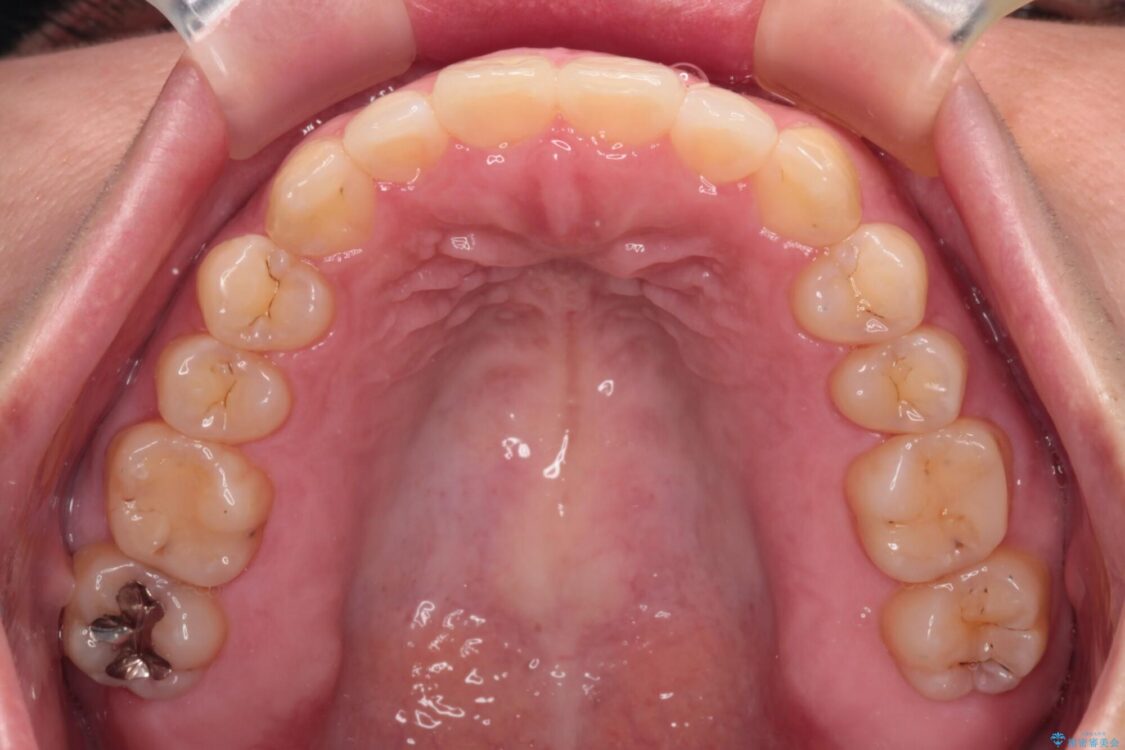

治療後

• 【モニター】カリエール・ディスタライザーを併用した八重歯のインビザライン矯正 治療後画像

治療後について

カリエールディスタライザーを併用したことで、すっきりとした口元になり、上下の正中を合わせることができました。